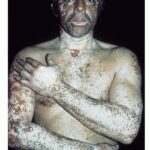

CLINICAL FINDINGS

Vitiligo is classified as segmental, acrofacial, generalized, and universal, or by pattern of involvement as focal, mixed, and mucosal types.

Depending on ethnic color, vitiligo is more or less conspicuous .

Depigmentation

Monobenzyl ether of hydroquinone (Monobenzone) is the only agent available in the United States and Europe for depigmenting residual normal skin in patients with extensive vitiligo. Monobenzone is a phenolic toxin that destroys epidermal melanocytes after protracted use. Monobenzone can therefore produce a uniform depigmented state that is cosmetically more acceptable for many patients than the contrast between normal and affected skin . Monobenzone is available as a 20 percent cream and can be formulated at concentrations up to 40 percent. The individual using monobenzone should avoid direct contact with others for 1 hour after application, as contact may cause depigmentation of others' skin. Monobenzone may also be irritating and allergic sensitization may occur.